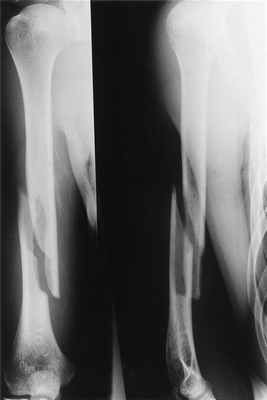

Пациентка с чрезвычайно тяжелым повреждением: тяжелым внутрисуставным переломом нижнего отдела плечевой кости с повреждением локтевого сустава с перелом средней трети локтевой кости со смещением отломков (дорожная травма).

Рентгенограмма до операции.

Выполнена операция: металлоостеосинтез плечевой кости пластинами LCP, анатомия локтевого сустава полностью восстановлена, остеосинтез локтевой кости стержнем с блокированием через небольшие разрезы-проколы (до 1 см.).

Гипсовая повязка после операции не применялась, сразу разрешена разработка движений в суставах конечности. Результат через 3 недели после операции. Уже видна хорошая функция конечности.

Результат через 4 мес. после операции. Функция конечности полностью восстановлена. Конечность ничем не отличается от здоровой.